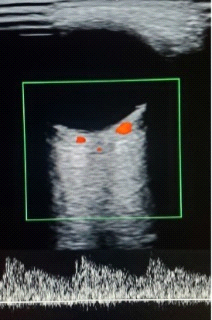

Ciliary arteries: arterial flow velocities are lower than those of the ophthalmic artery lateral to the optic nerve and have a uniform thickness (Figure 4).

Figure 4 Spectrum of posterior ciliary arteries.